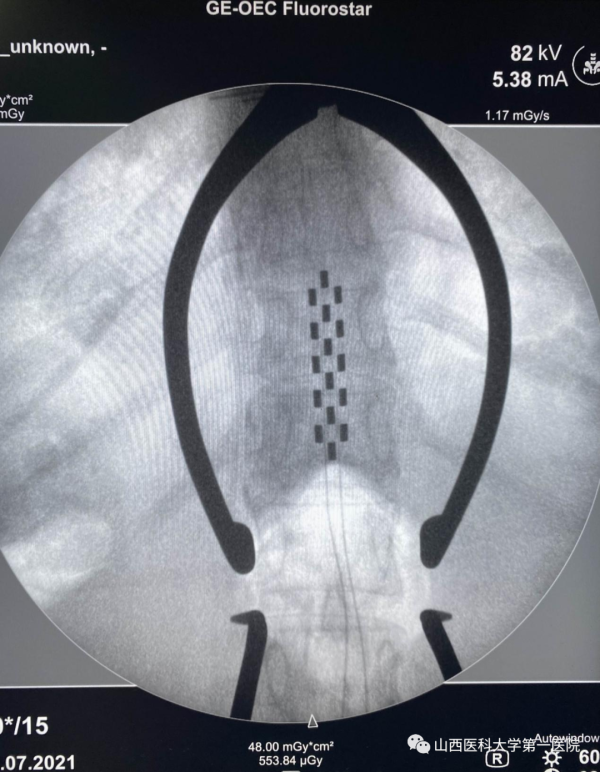

截肢的噩耗对张老太及家人来说无疑是晴天霹雳,经过多方打听,一家人来到山西医科大学第一医院神经外科找到了连世忠主任医师。他告诉张老太脊髓电刺激技术对糖尿病足患者保留肢体、降低截肢率有很好的效果。张老太仿佛找到了救命稻草一样,果断办理住院接受治疗。经过科学系统的术前评估,连世忠主任医师团队给张老太成功实施脊髓电刺激手术。

做完手术开机通电后,张老太感觉自己的双腿酥酥麻麻的,明显感到双下肢有一股暖流,脚一点都不疼了。开机当晚,张老太终于睡了一个久违的好觉。术后一个月,张老太复查情况良好,腿部色素沉着明显减轻,皮肤又恢复了光泽,右脚大拇指的溃疡已经痊愈,创伤的愈合对糖尿病患者来说比什么都可贵。红外热成像检查可以看到其下肢温度较术前明显改善,温度的提高反映了血液供应的恢复。张老太再也不用忍受下肢剧痛的折磨,终于可以下地走路了。